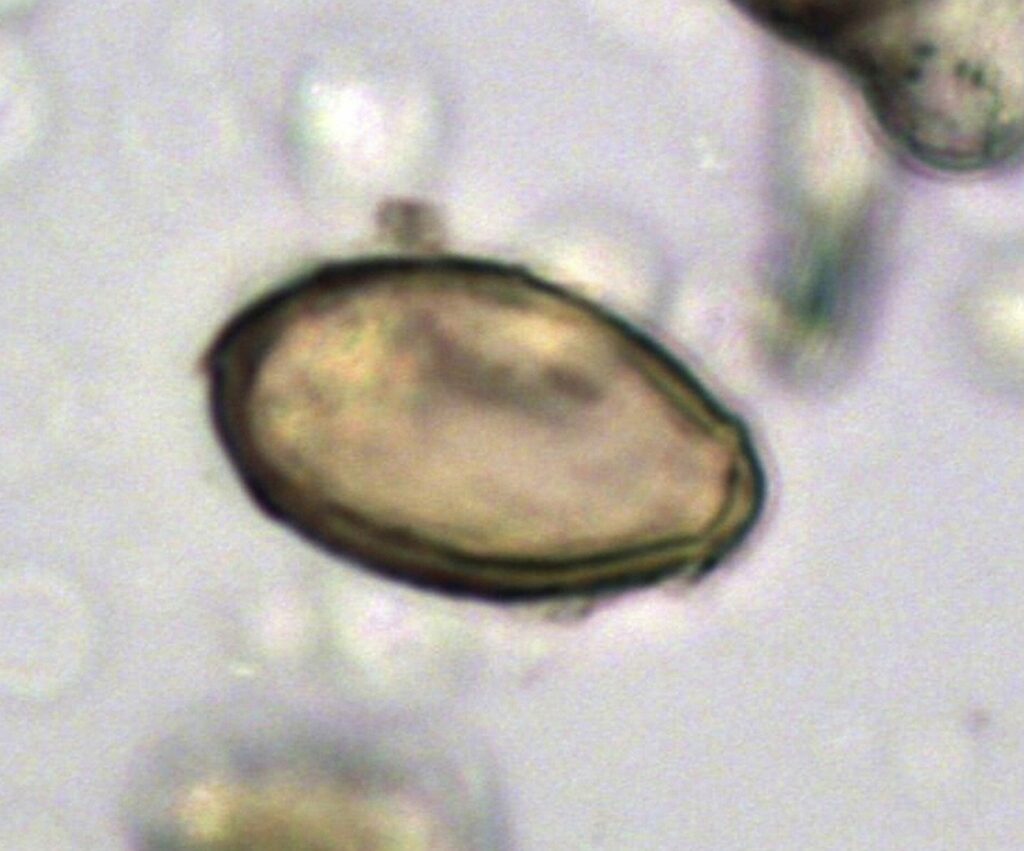

Ciuma este o infecție bacteriană care a cauzat moartea a milioane de oameni în Europa secolului al XIV-lea. În prezent, această afecțiune este tratabilă cu antibiotice.

Forma bubonică a ciumei este cea mai cunoscută manifestare a infecției. Această boală se răspândește în mod natural între rozătoare, cum ar fi șobolanii și câinii de prerie.

Ciuma septicemică se extinde prin întregul organism al individului, în timp ce ciuma pneumonică afectează în special plămânii. Ciuma pneumonică reprezintă forma cea mai letală și cu cea mai rapidă transmisibilitate.

Agentul patogen este transmis prin mușcătura puricilor infectați, putând afecta rozătoarele, animalele de companie sau oamenii.